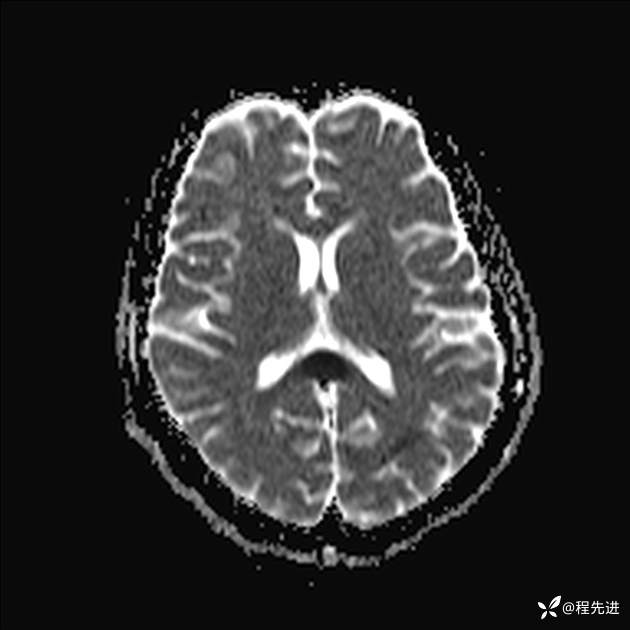

【患者信息】:女,25岁

【现病史及既往史】:言语含糊、意识状态改变1天。有下段剖宫产术10天病史。

【检查】